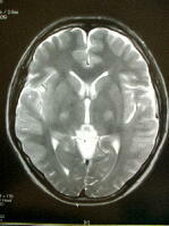

脳の病気で1番怖いものの1つに『くも膜下出血』があります.これは脳の血管にできた『こぶ』が破裂して起こる病気で約半数が命を落とします.脳ドックでは,MRIを用いて未然にこの『こぶ』を発見したり,脳梗塞の前兆や初期の脳腫瘍を発見することを目的としているほか,血液検査,心電図により脳卒中の危険因子をチェックすることを目的としています.当院では日本脳ドック学会のガイドラインに準拠した検査を行っています.現在1ヶ月あたり50-100件の検査実績がございます.万が一異常が発見された場合はご相談の上,適切かつご希望の病院にご紹介いたします.

7,MRI検査(頭部の断層撮影,頭部と頚部の血管撮影)